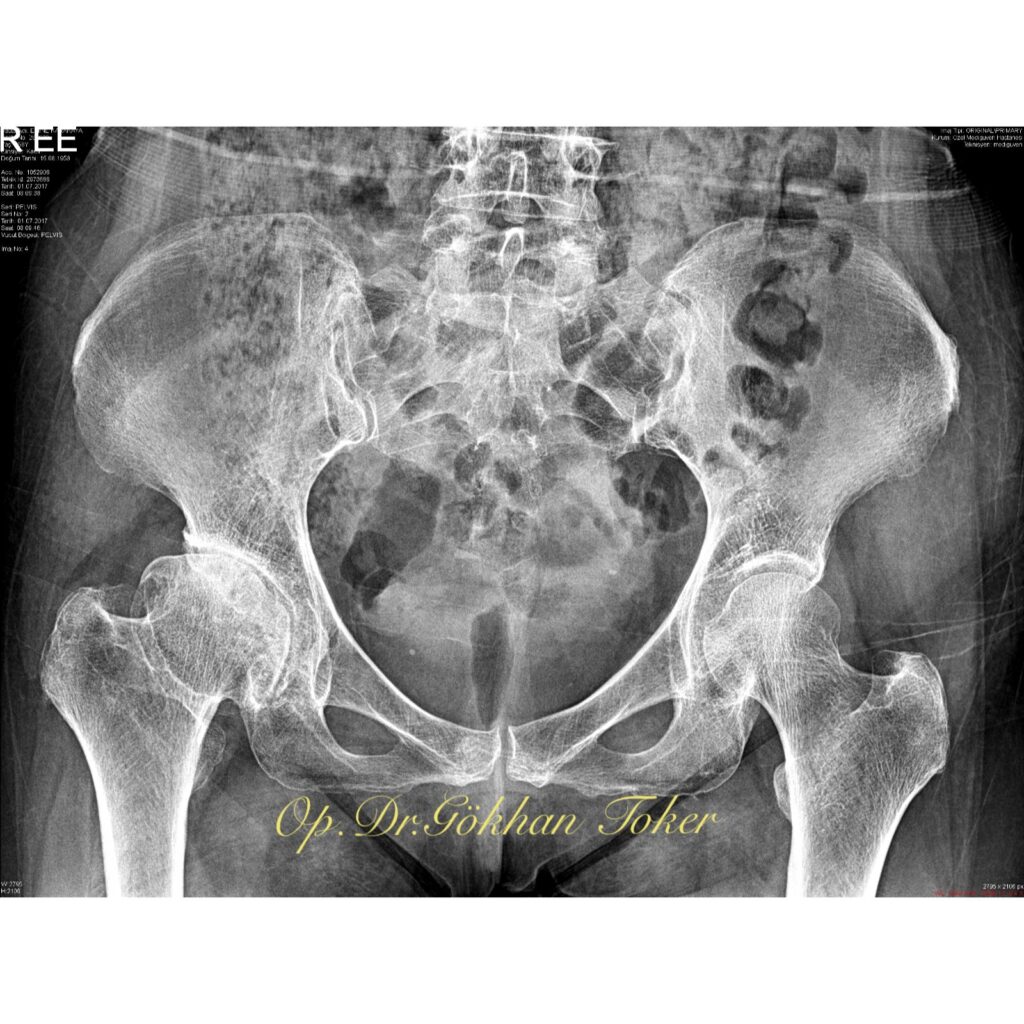

Vaka Örnekleri